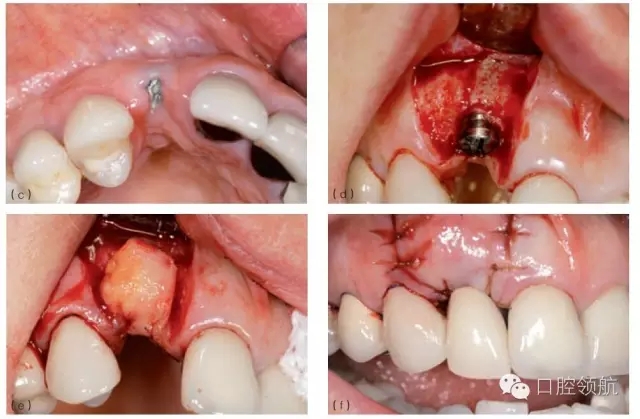

當(dāng)植入位置不佳不能以軟組織移植來(lái)挽救,而患者又要求達(dá)到良好的美學(xué)效果,除了取出種植體重新開(kāi)始之外,別無(wú)選擇。取出種植體后通常需要進(jìn)行骨增量,之后在正確位置上植入新種植體。對(duì)于局部骨增量,推薦引導(dǎo)骨再生(GBR)技術(shù),可同期或分階段進(jìn)行。外科方法的選擇主要取決于取出種植體時(shí)造成骨缺損的范圍和形態(tài)。任何時(shí)候,盡量在種植體植入同期行GBR,這時(shí)候一般是二壁骨缺損,如此可以避免患者接受額外的手術(shù)程序。然而,取出種植體導(dǎo)致的一壁骨缺損需要分階段的方式,首次骨增量采用自體骨塊移植加膠原膜覆蓋,5~6月后再植入種植體。這些治療需要患者和醫(yī)生的合作,通常可以獲得不錯(cuò)的美學(xué)效果(圖8.26a~g)。

圖8.26 (a)一個(gè)非常嚴(yán)重的病例:上頜前牙區(qū)植入3顆種植體。首先,考慮到美學(xué)效果,應(yīng)該只在8號(hào)和11號(hào)位點(diǎn)植入2顆種植體;其次,8號(hào)種植體冠向植入位置不佳伴肩臺(tái)外露。3顆種植體都需要取出。(b)種植體取出術(shù)中應(yīng)做避開(kāi)齦乳頭的小切口,盡量減少創(chuàng)傷。(c)翻開(kāi)黏骨膜瓣后清楚可見(jiàn)唇側(cè)骨缺損。在種植體鄰面小心去骨,盡量減少唇側(cè)去骨。(d)取出3顆種植體后的臨床情況。骨缺損處清創(chuàng),膠原塞填充。(e)手術(shù)完成,初期傷口關(guān)閉需達(dá)到軟組織完整覆蓋缺牙區(qū)。6~8周后種植體植入并同期行GBR。(f)植入2顆種植體和局部GBR骨增量治療3年后的效果。用低替代物含量的骨充填物(去蛋白小牛骨礦化基質(zhì))行橋體區(qū)域垂直骨增量。(g)3年隨訪檢查的X線片。新植入的2顆種植體顯示出穩(wěn)定的種植體周骨水平,尤其在橋體區(qū)域。